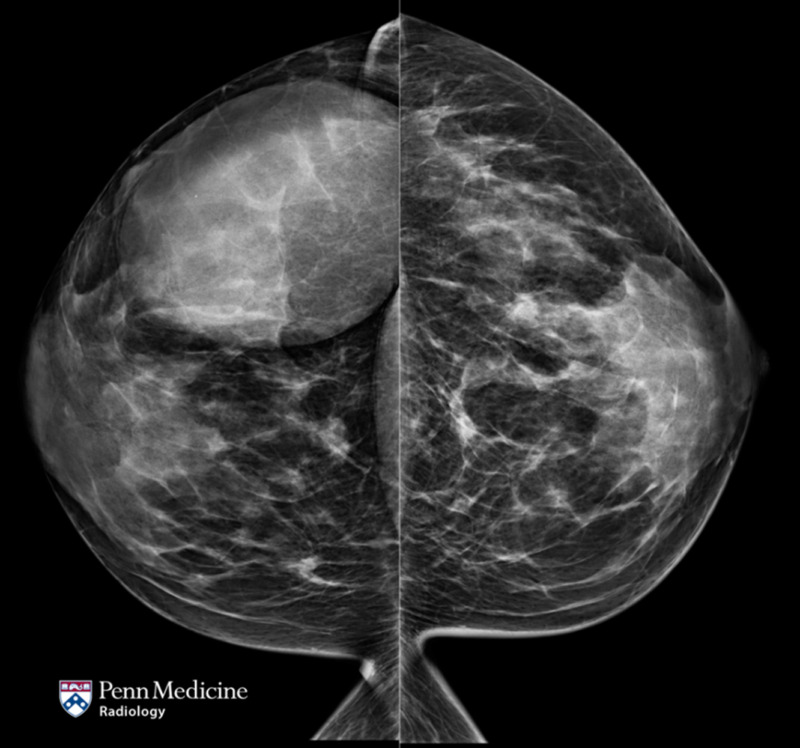

35-year-old woman with progressive pain and swelling in left lower leg

A 35-year-old woman presented to the emergency department with a three-week history of progressive pain and swelling in her left lower leg.

Published Date: February 13, 2026

Tags:

Body

,

CT

MRI

Musculoskeletal

X-Ray